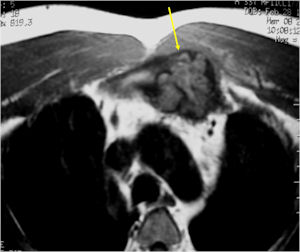

CT Scan:

- More useful for detecting mineralization and evaluating extent of bone destruction than plain X-ray

MRI:

- Also useful in determining extent

- There is often extensive edema around the tumor in the surrounding bone and soft tissues that can lead to a misdiagnosis of a malignant tumor.